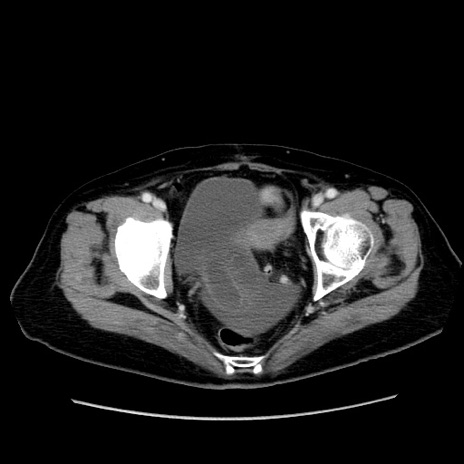

症例19(横断像)

【症例】80歳代女性

【主訴】下腹部痛

【現病歴】約8時間前より下腹部痛の出現あり、救急外来受診。

【既往歴】両側付属器切除

【身体所見】意識清明、下腹部正中に手術痕あり、その部位に一致して圧痛と反跳痛あり。腸蠕動音は亢進。

【データ】WBC 9300、CRP 0.15